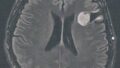

【備忘録】グリオーマ・びまん性星細胞腫:手術後132ヶ月目の検査 1)グリオーマ神経膠腫(脳腫瘍) 2025.06.262025.07.31 手術から11年が経過した。半年ごとの定期検査です。 目次 検査概要診断結果 検査概要 びまん性星細胞腫グレード2(悪性転化しやすい腫瘍) MRI検査: 造影剤なし / 造影剤あり 造影剤ありの場合:4時間前から絶食し、MRIの1時間前に血液検査を済ませる。 診断結果 着実に大きくなっている 症状が出る前でも手術した方が良い 手術の時期を考える FLAIR Axi FS+ SPAIR FLAIR Ob.Cor FS+ 主観的心痛度:★★★★★(ついに来たかという感じ。いつ手術するか。。。)